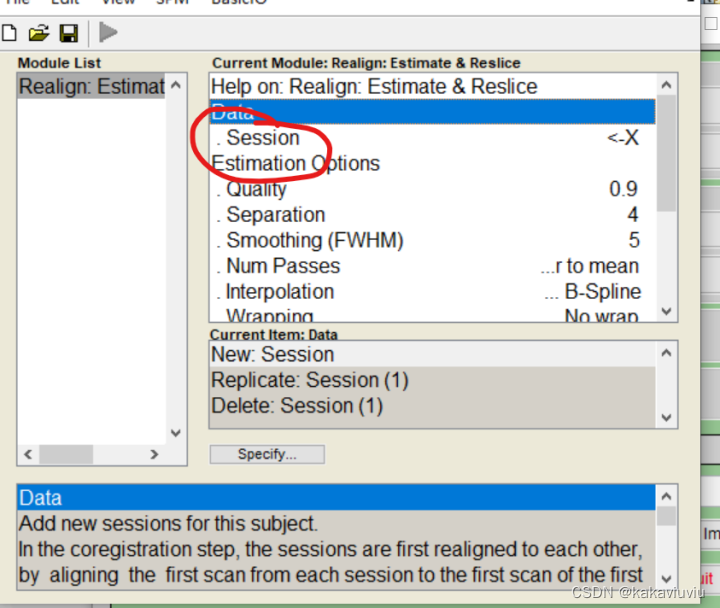

(3)R:realign 头动校正

双击

只筛选以a为开头的文件(上一步生成的时间校正后的文件)

文件选中就可以运行了。Num passes 后面的register to mean:选中to fist 与第一张图象对齐,to mean,就是与平均的对齐